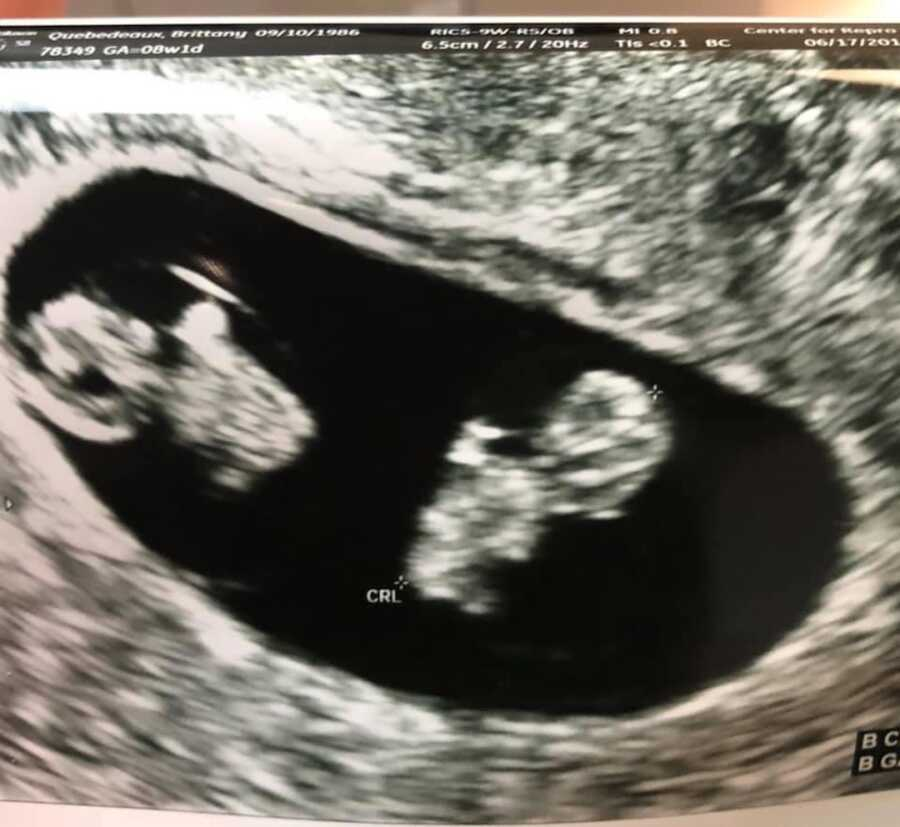

The line was dark, darker than any she’d seen. At the clinic, her numbers more than doubled. Relief rushed in, tangled with fear. An ultrasound showed nothing yet, not even a sac, so they warned it could be ectopic and asked her to return in a week. Seven long days later, there was a heartbeat, one steady, tiny thrum. At the eight-week scan, she went alone, expecting a quick look. The tech smiled and turned the screen: two babies.

The single embryo had split into identical twins. Joy arrived with new risks: mono-di twins sharing one sac but with a thin divider and separate fluid. The weeks that followed were a marathon of specialist visits in Houston and regular OB checkups, sometimes weekly, with two-hour ultrasounds to watch for twin-to-twin transfusion and heart issues. Scares came and went. Then, pink smoke at the reveal, two girls.